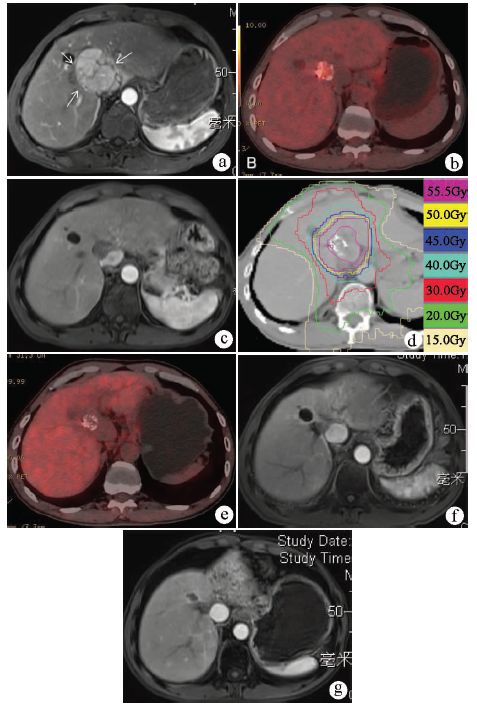

如果肝肿瘤较大,SBRT容易带来肝损伤。经过介入栓塞化疗后,肝肿瘤明显缩小,直径一般小于5 cm,特别是单发肿瘤,则给予SBRT,从而使不能根治的肝内肿瘤转化为可根治。我国香港报道[13]显示,49例患者接受介入治疗后给予SBRT, 较98例(1∶2配对)接受单纯介入治疗的对照组,SBRT者肿瘤局控率和生存期都远有优势。病例5是局限肝内的大肝癌患者,肿瘤靠近肝门不能手术,介入后肿瘤降期,调整为SBRT,获得完全缓解(图5)。

注:a,MRI显示肝门部7.5 cm病灶,动脉期明显增强,肝细胞癌的影像学表现;b,6次介入后PET-CT示肿瘤缩小,部分碘油沉积,瘤内糖代谢较高,SUV值4.7 g/ml;c,7次介入和7次FOLFOX4化疗,SBRT前,MRI示下腔静脉旁病灶1.8 cm,动脉期无强化;d,CT上勾画的靶区制定放疗计划,SBRT肿瘤等剂量分布曲线,55.5 Gy/15次;e,SBRT后11个月,PET-CT显示肿瘤无糖代谢;f,SBRT后16个月随访MRI,与放疗前(c)比较,病灶缩小到0.9 cm,无血供;g,SBRT后4年随访MRI,病灶大小稳定,无血供;h,整个治疗过程中的AFP变化。SBRT后,AFP降至最低点。

图5 不能手术切除大肝癌接受介入后转化为小肝癌,接受SBRT